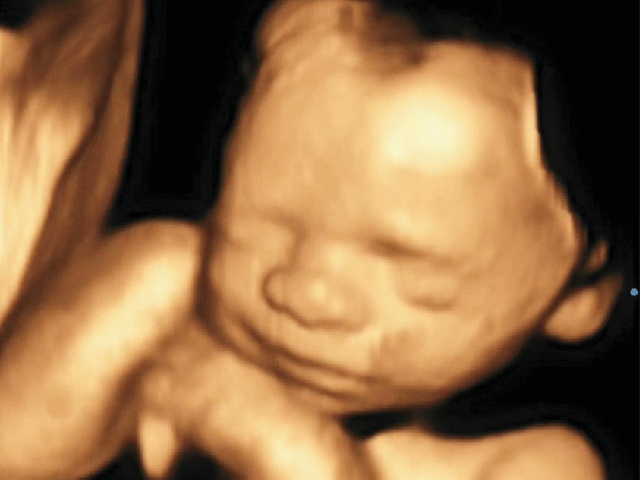

Рис. 17. 3D-визуализация расщелины губы и нёба (стрелка) в 27 нед беременности.